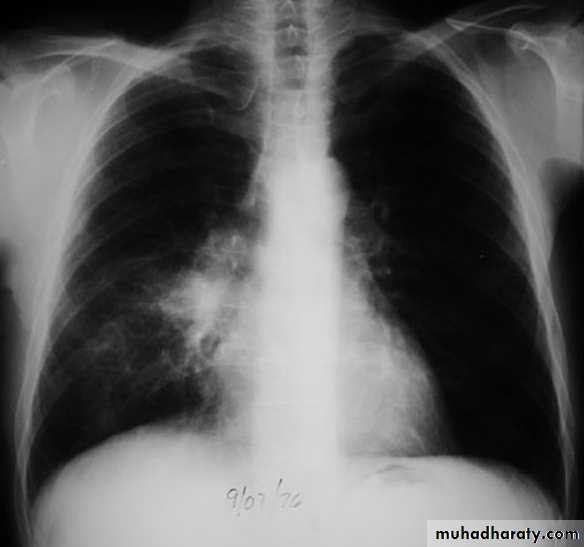

Lingular consolidation-PA. Patchy effacement of the left heart border.

chest practice